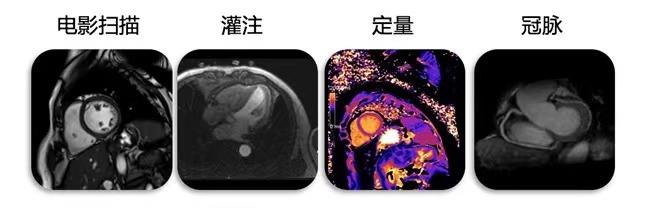

生命感知自由心脏成像平台

心脏成像一直是磁共振扫描的难点。传统的磁共振扫描心脏不仅对于患者的心率有要求,而且心脏节律也要求规律。此外,扫描过程中要求患者多次屏气进行扫描,大多数心脏疾病的患者都很难成功完成扫描。

而生命感知成像系统,让无对比剂心脏冠脉成像得以实现,让心脏自由呼吸成像得以实现。不仅大幅度提高患者扫描时的舒适性,而且保证运动脏器极高成像质量。